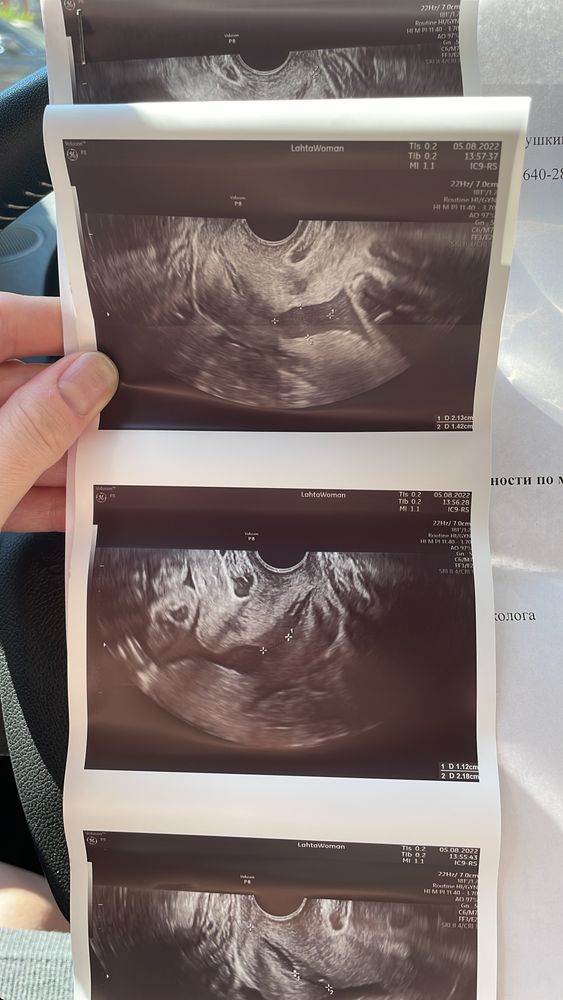

Девочки. SOS. Цервикометрия

УЗИ, КТГ, доплер(Фото внутри) Посмотрите, пожалуйста!

мониторю шейку, сегодня срок 29+1. Длина шейки 36мм, хорошая, но появилось воронкообразное расширение. Написала гине, жду ответа от неё. Успокойте, скажите, что это норма!! Не рано ли шейка сглаживаться начала?

upd: повтор цервикометрии через неделю. Все хорошо. Врач просто попалась неумная мягко говоря